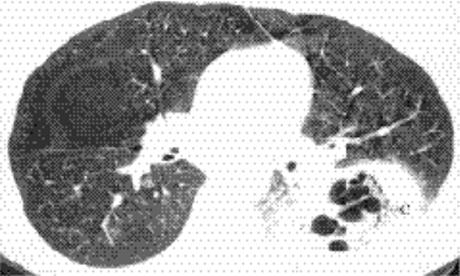

Cavitating consolidation (Figs. 5.13 and 5.14) suggests bacteria or fungi. S. aureus, Klebsiella, anaerobes, and Mycobacterium tuberculosiscommonly cause cavitation. Pneumatoceles may result in a similar appearance (Fig. 5.15) and suggest S. aureus or S. pneumoniae.Emphysematous bullae within consolidated lung may mimic cavities.

Figure 5.14 Cavitary pneumonia (C) at computed tomography.